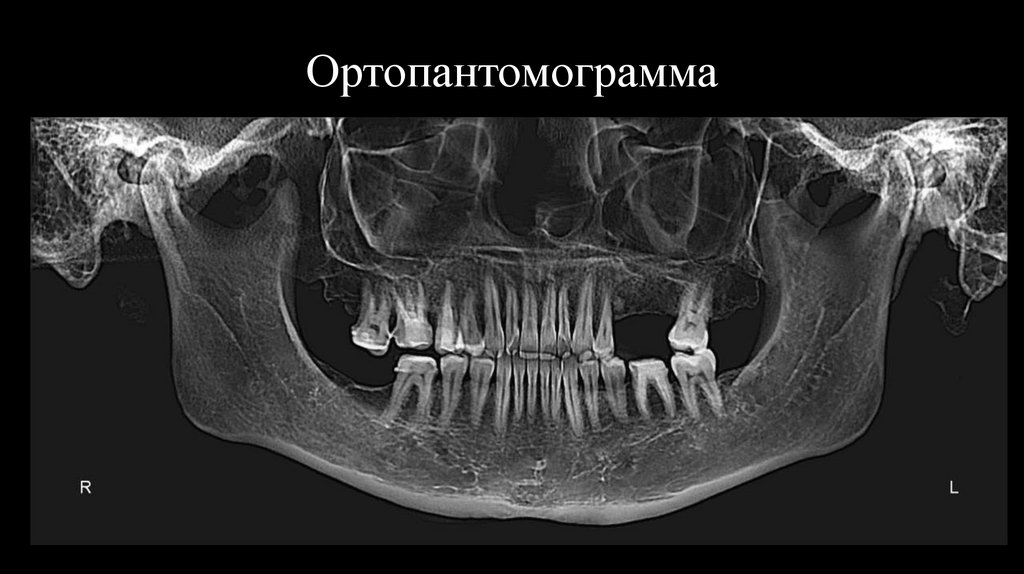

10. Ортопантомограмма

11.

Объективно:

Контуры лица симметричны. Пальпация жевательных

мышц и ВНЧС безболезненна.

Хруст и щелчки в ВНЧС не аускультируется.

Девиация вправо.